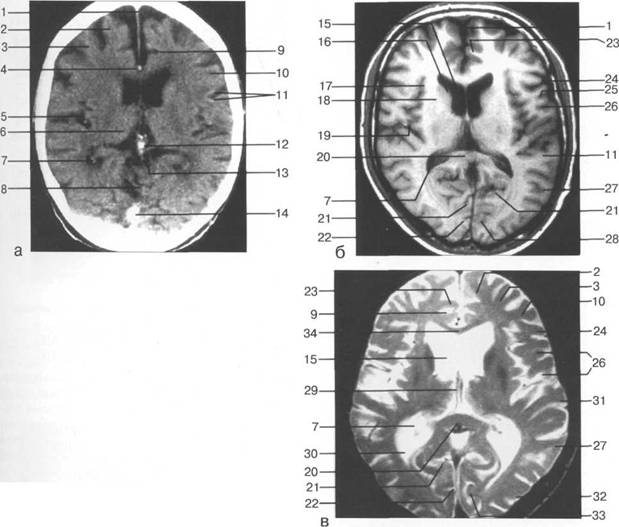

височная доля; 17 - полушарие мозжечка; 18 - |

редняя мозговая артерия; 31 - межножковая цистерна.

мие; 26 - поясная борозда; 27 - головка хвостатого ядра; 28 - бледный шар; 29 - височный рог боково

цистерна четверохолмия; 14 -прямой синус; 15 -лобный рог; 16 - головка хвостатого ядра; 17 -перед

III ди зрительного бугра идет ретроталамическая цистерна, ориентированная во фронтальной